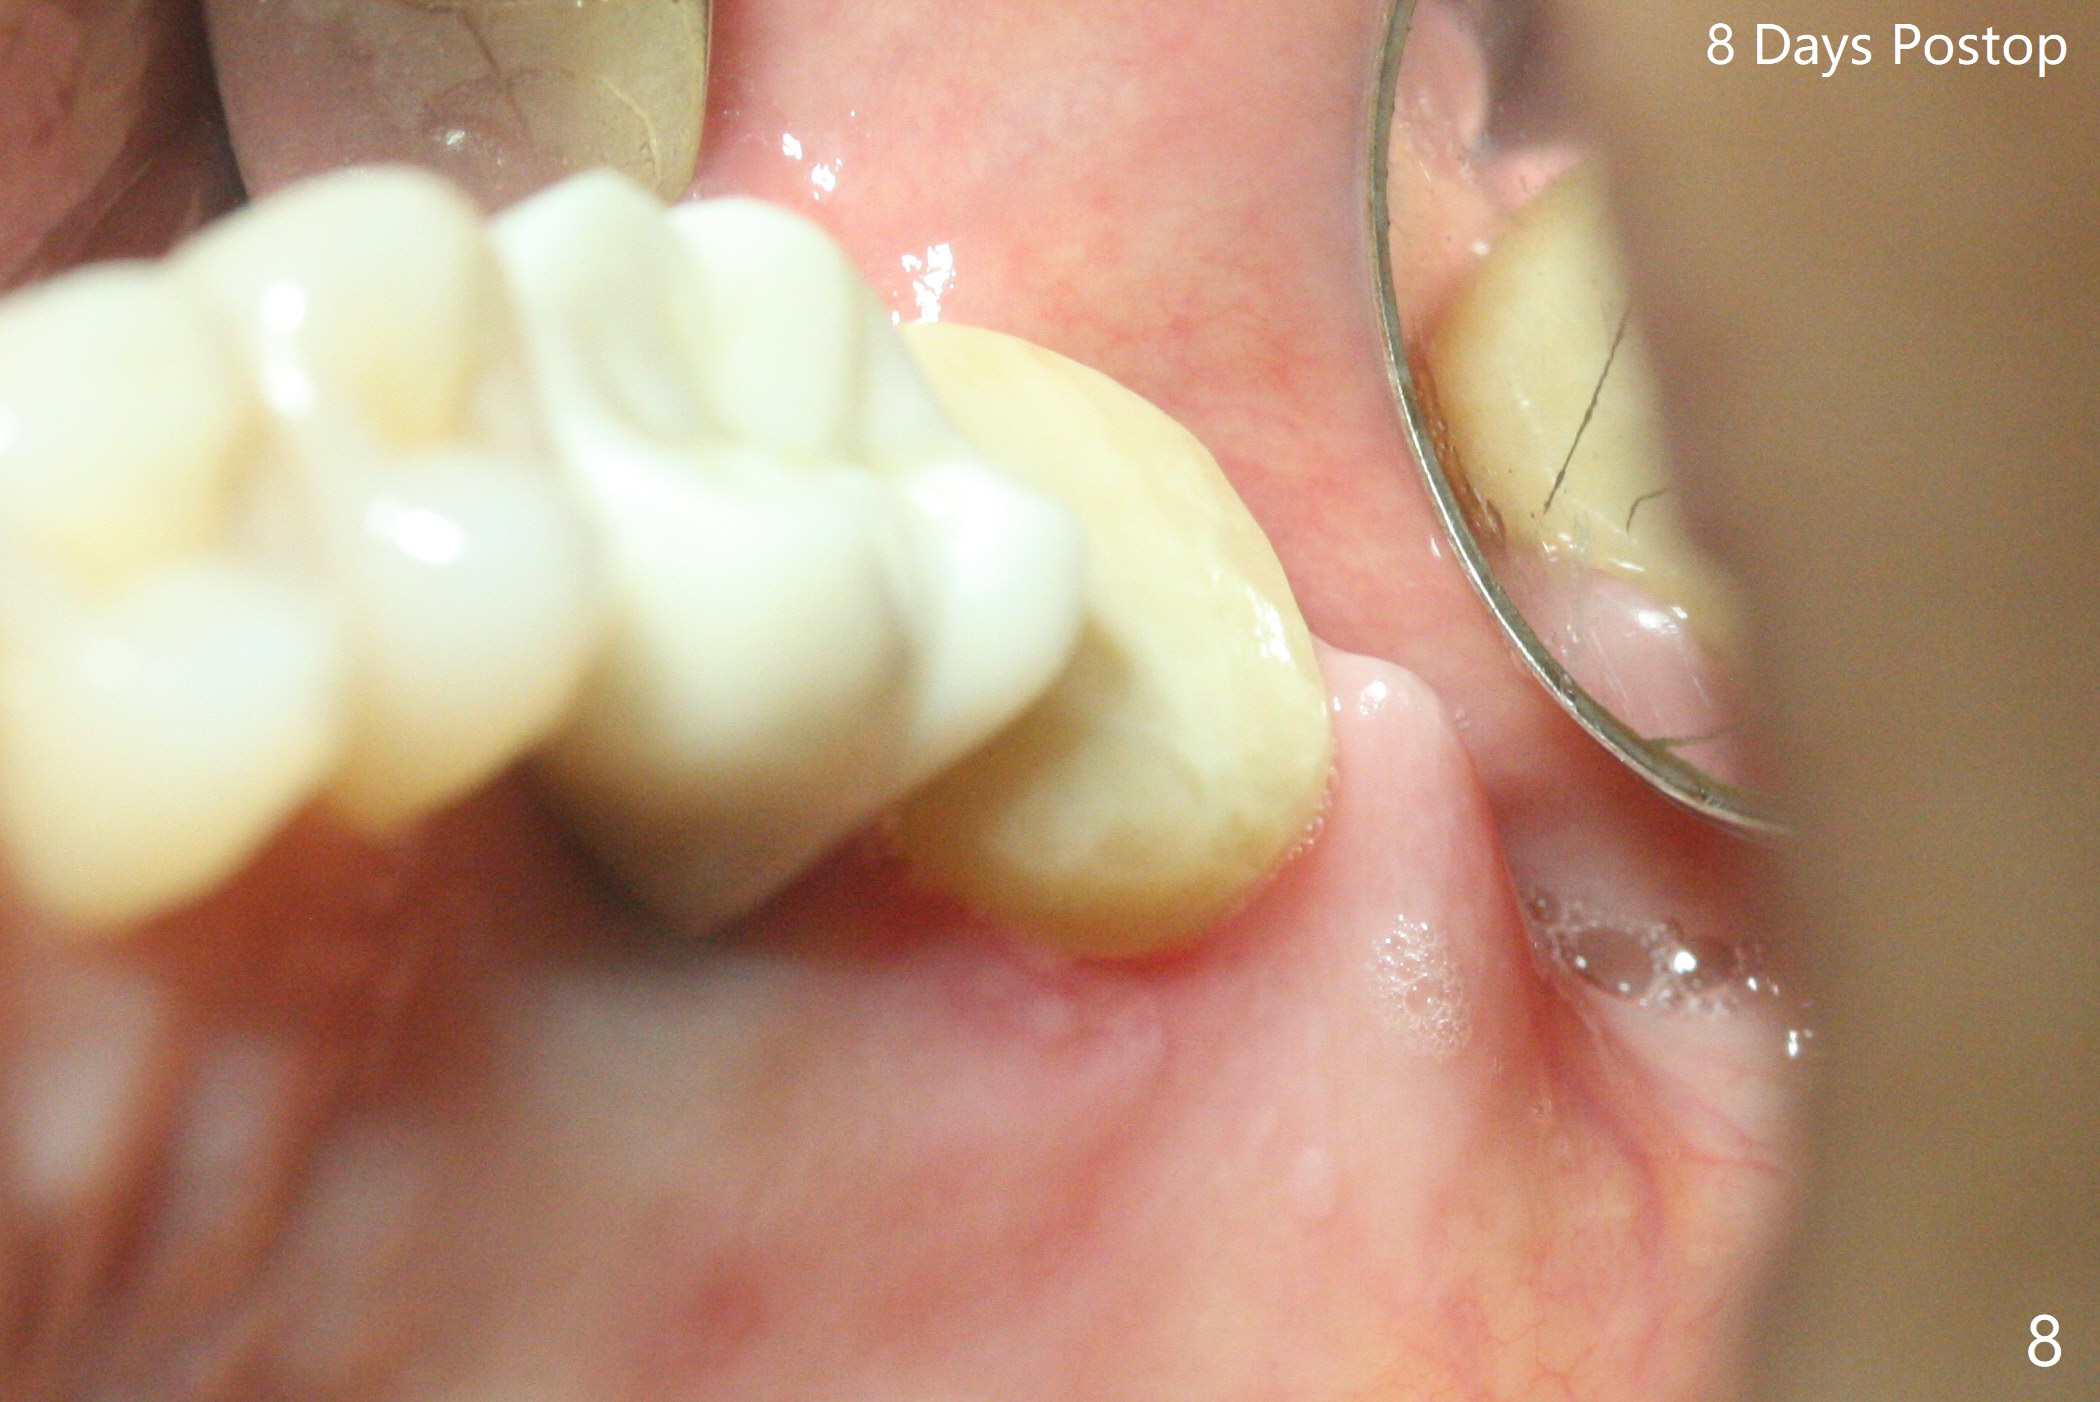

术前15号牙远中隐裂(图一:^),14号牙植体光滑面腭侧暴露(8年前腭侧窝植入),但是牙龈健康(图二)。14号牙牙槽窝没有肉芽组织,利用导板(Shinning Oral Scanner)完成3.5毫米钻洞,无法使用圆钻做内提升,改用4x10毫米报废植体提升,不幸窦膜好像破裂(因为薄),塞入半块PRF膜,促进修复,然后使用4.5x10毫米报废植体扩大植牙床(图三,四),无意达到部分提升(*),取出报废植体,发现植牙床没有穿孔了,加入少量粘性骨粉(图五:S(即使在窦内不容易分散))后,植入正式植体和基台。植体周围间隙(图五:*),使用刮匙,牙周探针,和长探针(图六)将骨粉输入深部(图七:*)。